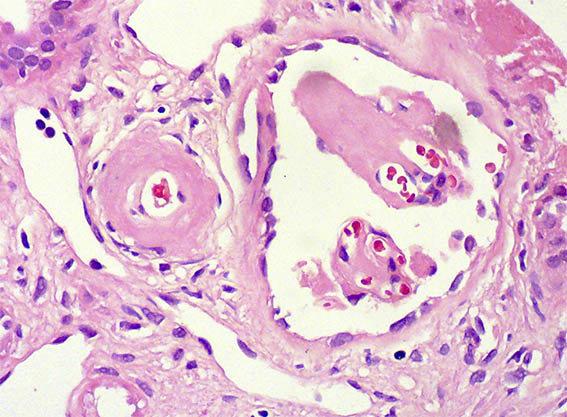

Figura 3.

H&E, X400.